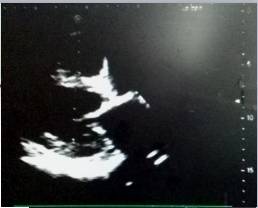

4、心脏彩超

●升主动脉增宽,全心增大,左室壁增厚。

●动脉瓣狭窄(中-重度)并关闭不全(轻度)。

●肺动脉高压(中度)。

●室间隔运动幅度减低。

●左心舒张功能减低。